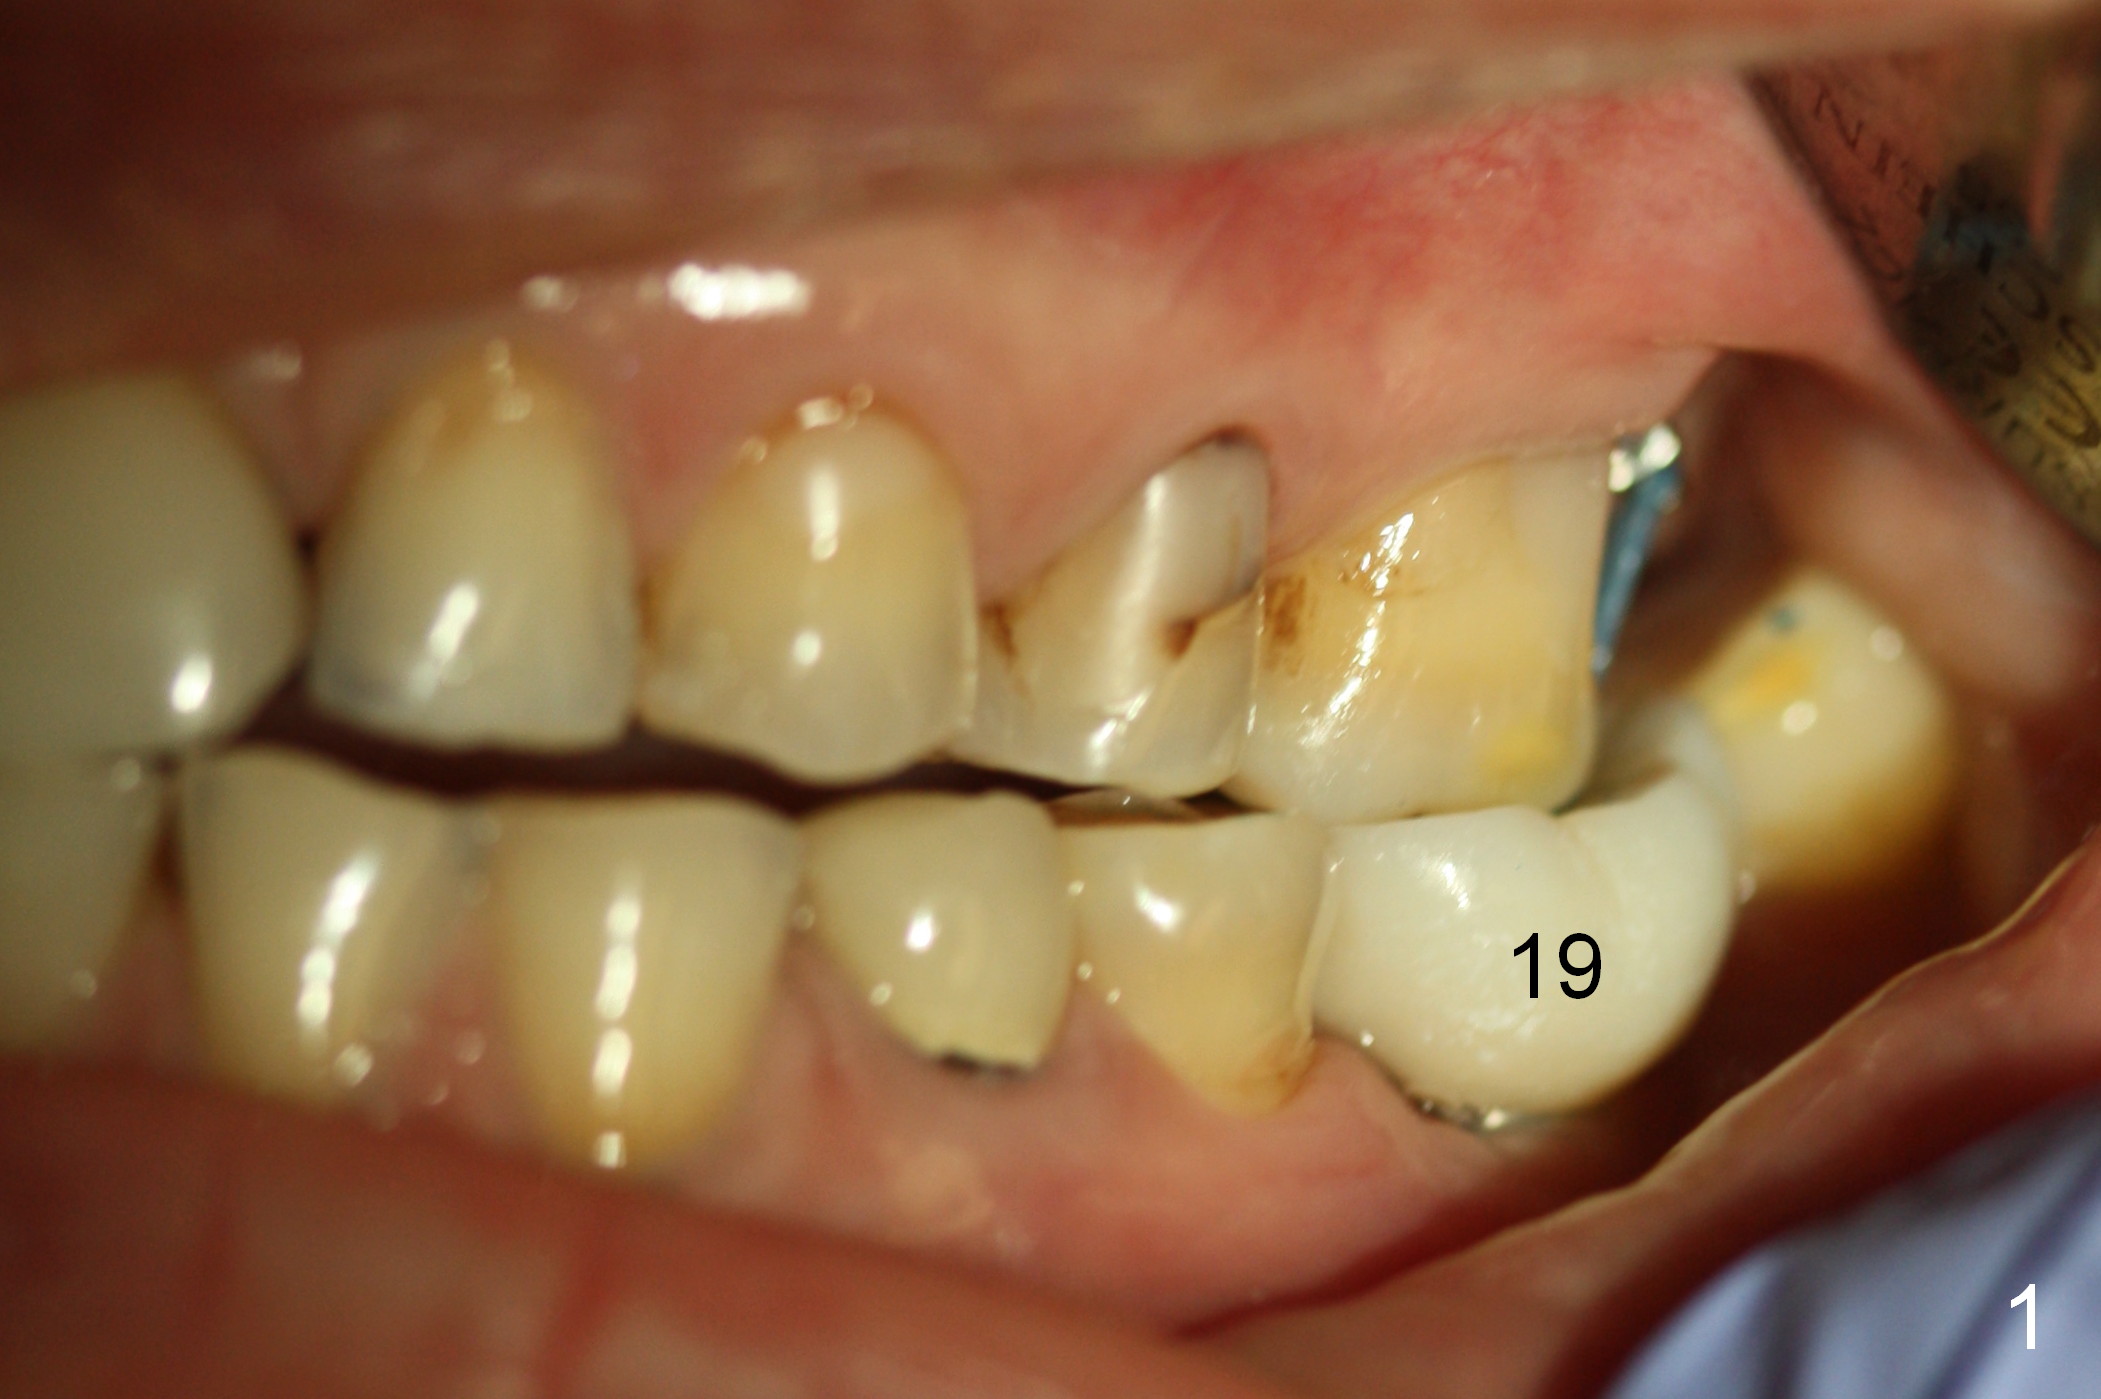

A 50-year-old lady had implant crown prep on 02/02/2015.  The intrusion of the opposing tooth was terminated (removing power chain).  She returned for crown cementation today (02/27/2015).  The temporary crown was broken for an unknown period of time.  When a Zirconium crown is seated at the site of #19, the rest of occlusion is off (Fig.1).  The contact with the neighboring teeth is within normal limit.

It appears that the opposing tooth is re-supraerupted.  Power chain of 4 is re-installed.  The crown is temporarily cemented.  Is there any other reason for the bite problem?  What can we do, especially what can we do to prevent crown cracking?

Jenny's reply: Does the cross bite affect the biting ? Or the buccolingual of the crown is too wide? To prevent crown cracking, I think we need to make the buccolingual narrower than other crowns.